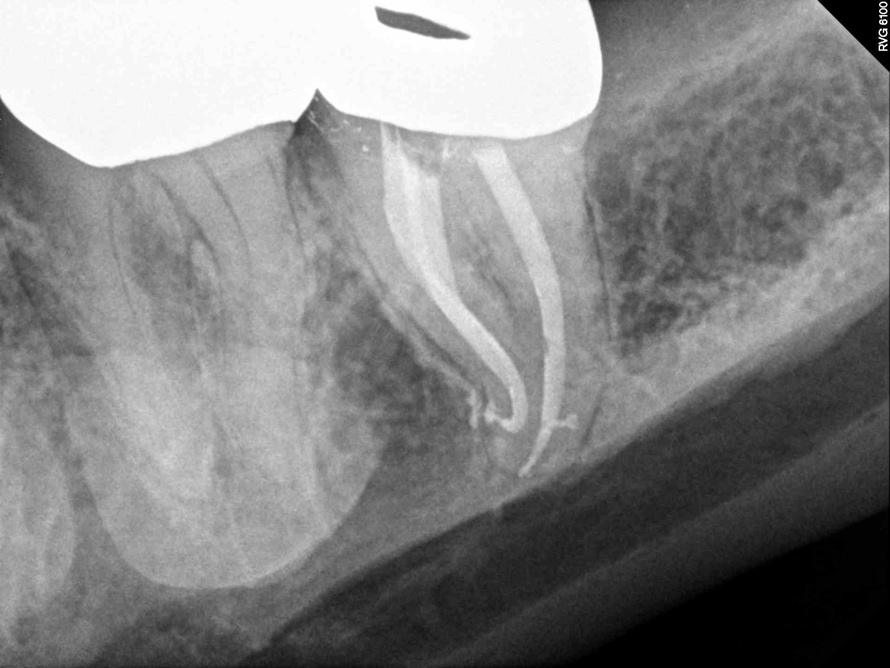

Fig 4.  Due to reported allergies to resin-based materials and eugenol, obturation was completed with a calcium hydroxide-based sealer (Figure 4 and Figure 5) with healing noted at a 1-year follow-up (Figure 6).

Figure 4

Fig 5.  Due to reported allergies to resin-based materials and eugenol, obturation was completed with a calcium hydroxide-based sealer (Figure 4 and Figure 5) with healing noted at a 1-year follow-up (Figure 6).

Figure 5